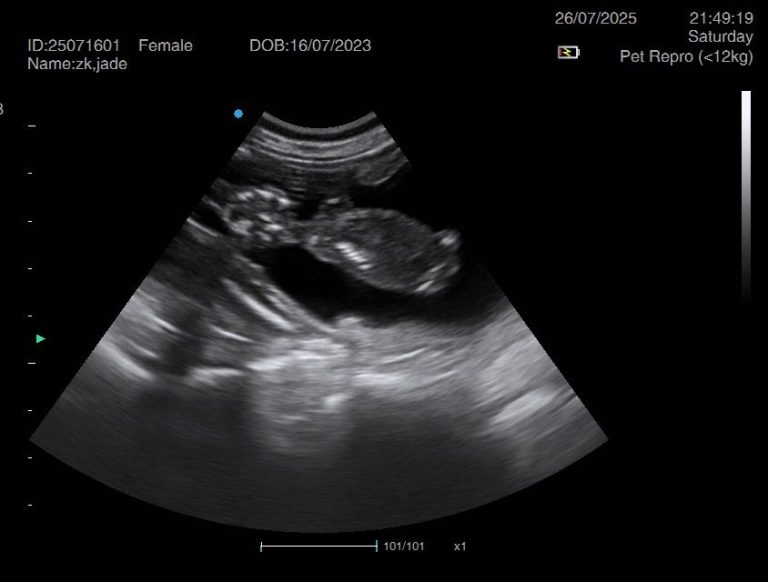

Ultrasound pregnancy scanning is a safe, non-invasive way to confirm pregnancy in dogs and cats, offering breeders and pet owners peace of mind and vital information to support responsible care. It allows us to detect gestational sacs, assess foetal development, and estimate litter size—all while ensuring the wellbeing of the animal.

Pregnancy can sometimes be detected as early as Day 18 post-mating, but scanning at this stage is not routinely recommended. Embryos are still developing and may not be clearly visible, and there is a natural risk of embryo resorption, which can lead to misleading or inconclusive results.

For the most accurate and reliable scan, we advise booking between Day 25 and Day 32, when pregnancy is more easily confirmed and foetal structures are clearer. If an early scan is performed and no pregnancy is detected, we offer a FREE complimentary re-scan after 7 days at the clinic to ensure clarity and support informed decision-making.